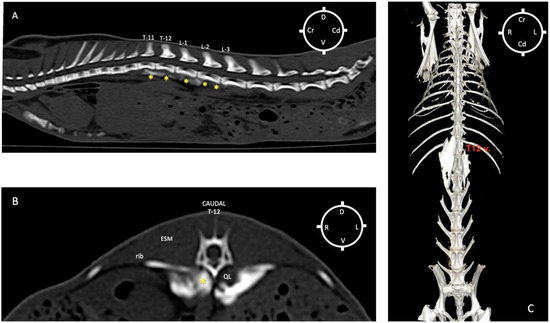

The first two out of four rabbit cadavers were used to understand the sono-anatomy and the relationship of the quadratus lumborum muscle and the thoraco-lumbar fascia surrounding the quadratus lumborum muscle and psoas muscles, and to design an ultrasound-guided quadratus lumborum muscle block approach specific for rabbits. For the needling, a ventral approach as reported in dogs and cats was first used [16,17] with the needle directed from the ventro-lateral to dorso-medial. However, during the sono-anatomy study, the abdominal structures such as the kidney and liver were very close to the needle path, resulting in an increased risk of potential internal organ damage (Figure 2A,B). Those concerns were confirmed during the anatomical dissections, as the dye solution was present within the kidney capsule (in three out of four thoraco-lumbar areas of two rabbits), likely due to its perforation when inserting the needle (Figure 2C).

Figure 2. Ultrasound-guided quadratus lumborum block (QLB) performed using a ventromedial approach. (A) Sono-anatomy of the thoracolumbar area at the level of the twelfth thoracic vertebra transverse process, arrows pointing out the thoracolumbar fascia, hyperechoic line. (B) In a different rabbit cadaver, the QLB was performed, using the ventromedial approach injecting a mixture of lidocaine 2%, permanent yellow tissue dye and iodine contrast (3:1:1). The needle is visible on the ultrasound image travelling close to the right kidney (RK). (C) After anatomical dissection, in the same rabbit of (B), the right kidney was exposed and part of the mixture was found in the kidney capsule after injection. ES m. erector spinae muscles; D dorsal; L lateral; M medial; PM m. psoas major muscle; Pm m. psoas minor muscle; QL m. quadratus lumborum muscle; RK right kidney; T12 TP transverse process of the twelfth thoracic vertebra; V ventral. Cyan blue dot indicates the marker of the ultrasound probe pointed dorsally.